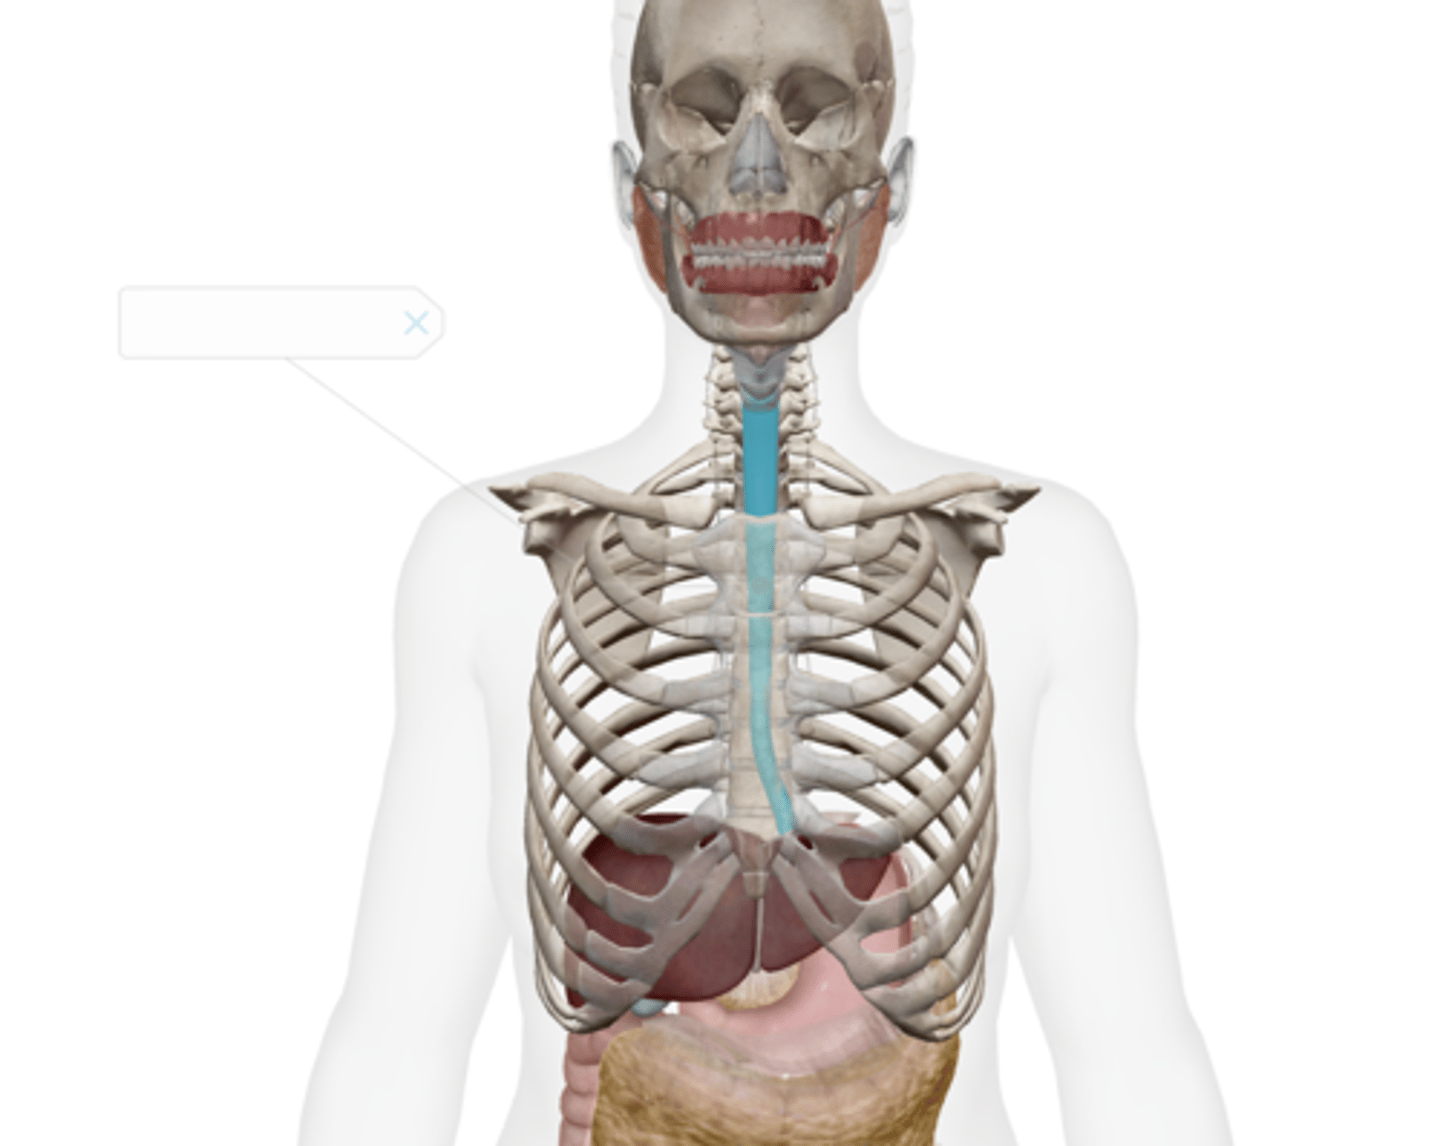

Esophagus